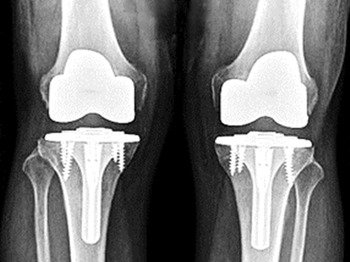

One of the most common joint replacement surgery in India. Only the worn out surfaces of the femur, tibia and patella (bones forming the knee joint) are reshaped, resurfaced and replaced with two metallic implants and a centre plastic piece.

Unlike a total knee replacement, in a partial knee replacement surgery, only the damaged part of the joint is replaced.